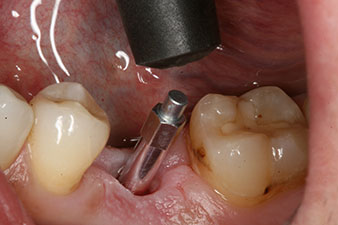

SmartPeg

Фиг. 4: Измерване със завит SmartPeg за определяне на коефициента на стабилност на импланта с интегрирания W&H Osstell ISQ модул.

Въртящият момент, използван за машинно-задвижвано поставяне, е 43 Ncm. Освен това, след завинтване на измервателния щифт (SmartPeg), специално пригоден за импланта, стойността на ISQ се измерва със сондата на W&H Osstell ISQ модула.

Този модул е допълнителна екстра към Implantmed на W&H и е закачен към имплантологичния мотор (виж фиг. 11). Липсата на ISQ стойност непосредствено след поставянето е 64 оровестибуларно и 68 мезиодистално (максимална стойност = 100).